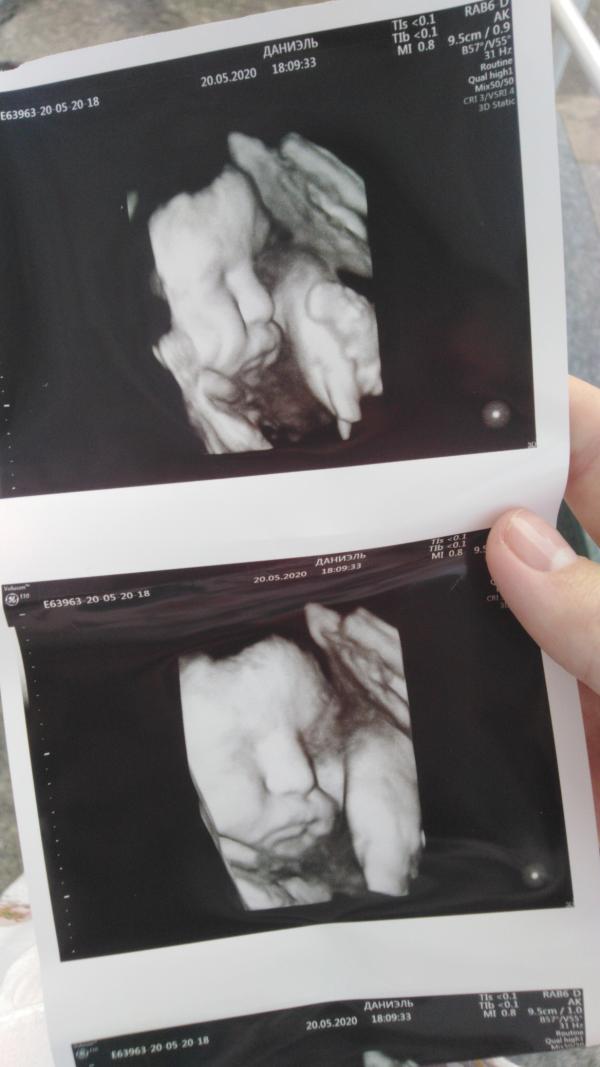

post image

Почти 39 недель 😍

Щекастый, выходи 😅🙈

Это был допплер, врач только личико посмотрела 3д

Но я делала не узи, а допплер. Фото так, в подарок😅